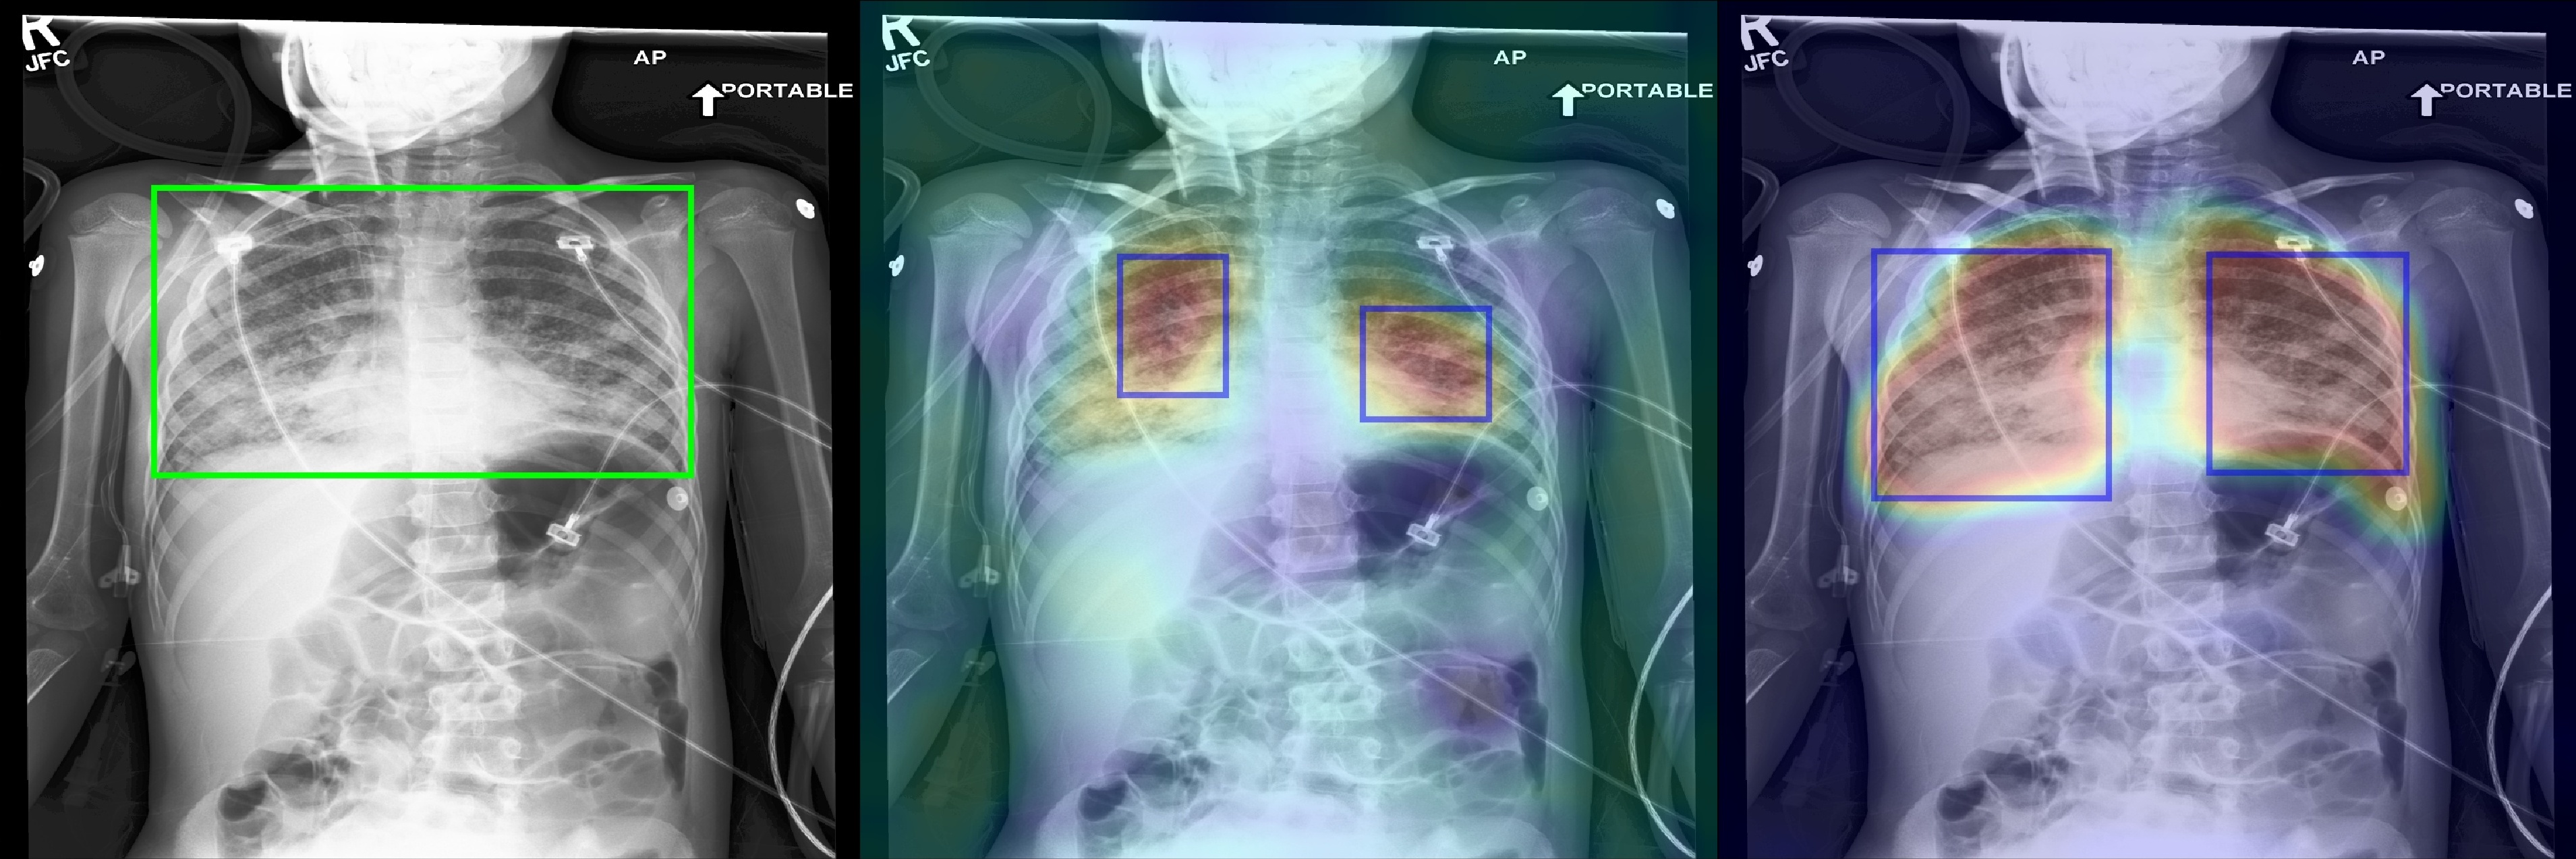

Figure 2 shows a few selected examples of the probability maps generated by PCAM pooling and the class activation maps generated by LSE pooling together with the predicted bounding boxes. Compared to the class activation maps, the probability maps are visually more clear with sharp boundaries around lesion regions. We attribute the improved visual quality to the probabilistic interpretation of the sigmoid-bounded class activation map and explicitly using it for training with global pooling.

We notice the probability maps generated by PCAM pooling tend to enlarge regions of interest in general than class activation maps from LSE pooling, especially when the ground truth regions are small, such as “Nodule” in Figure 2. This may explain the fact that PCAM pooling has relatively larger average false positives than CAM with LSE pooling.

(d) Pneumonia

Figure 2: Selected samples of localization heatmaps and their bounding boxes generated by LSE pooling and PCAM pooling on the test set of ChestX-ray14 [7]. In each subfigure, the left panel is the original chest X-ray with the ground truth bounding boxes (green), the middle panel is the class activation map and predicted bounding boxes (blue) by LSE pooling, the right panel is the probability map and predicted bounding boxes (blue) by PCAM pooling.